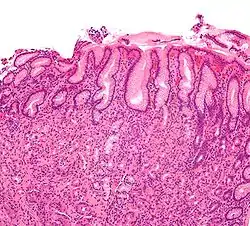

Гастри́т (лат. gastritis, от др.-греч. γαστήρ [gaster] «желудок» + суффикс -itis «воспаление») — воспалительные или воспалительно-дистрофические изменения слизистой оболочки желудка; длительно протекающее заболевание, характеризуется дистрофически-воспалительными изменениями, протекает с нарушением регенерации, а также с атрофией эпителиальных клеток и замещением нормальных желёз на фиброзную ткань.

Катаральный гастрит (лат. gastritis catarrhalis, син. простой гастрит, банальный гастрит) является чаще всего следствием пищевых отравлений и неправильного питания. Он характеризуется инфильтрацией лейкоцитов в слизистую оболочку желудка, воспалительной гиперемией, дистрофическими изменениями эпителия.